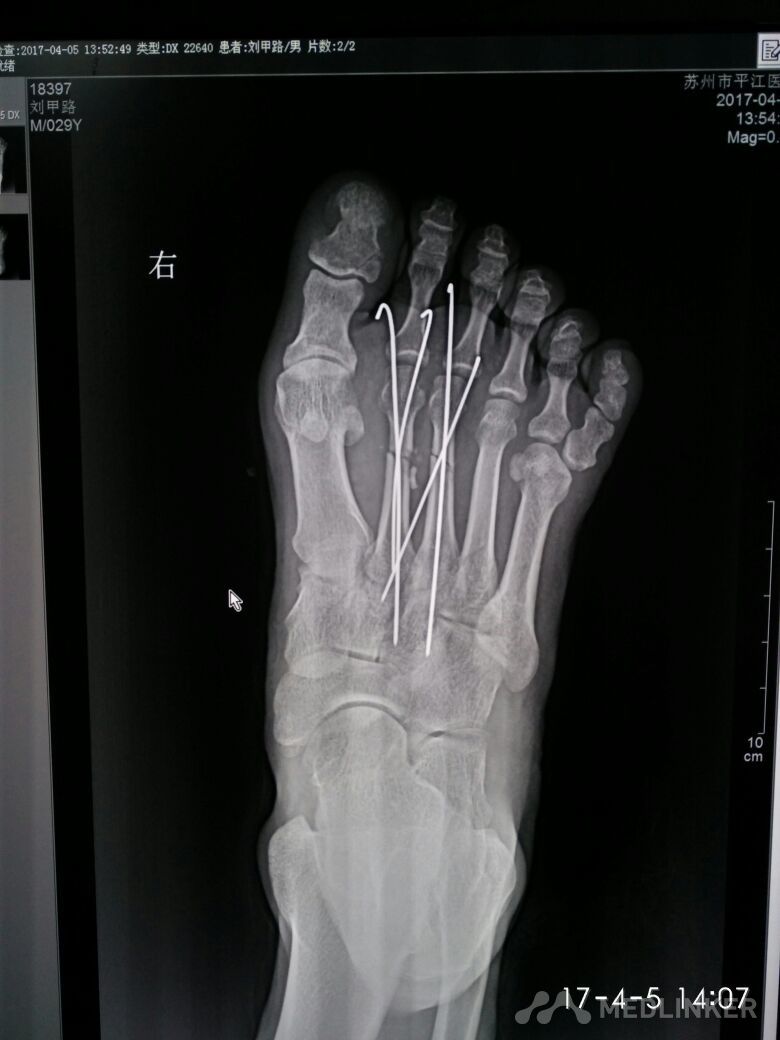

多趾畸形

请教各位诊断报告上怎么描述?